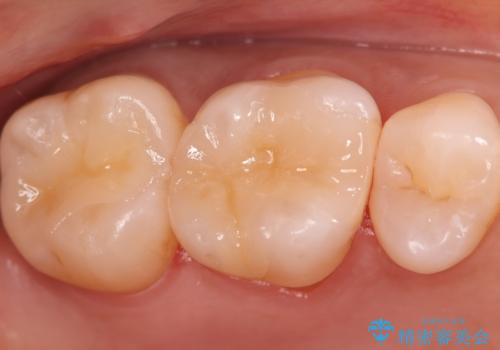

銀歯の下の虫歯|オールセラミッククラウン

担当医 河野豊嘉

奥歯に虫歯があると言われた セラミッククラウンでキレイで長持ちする歯へ

担当医 榊原康平